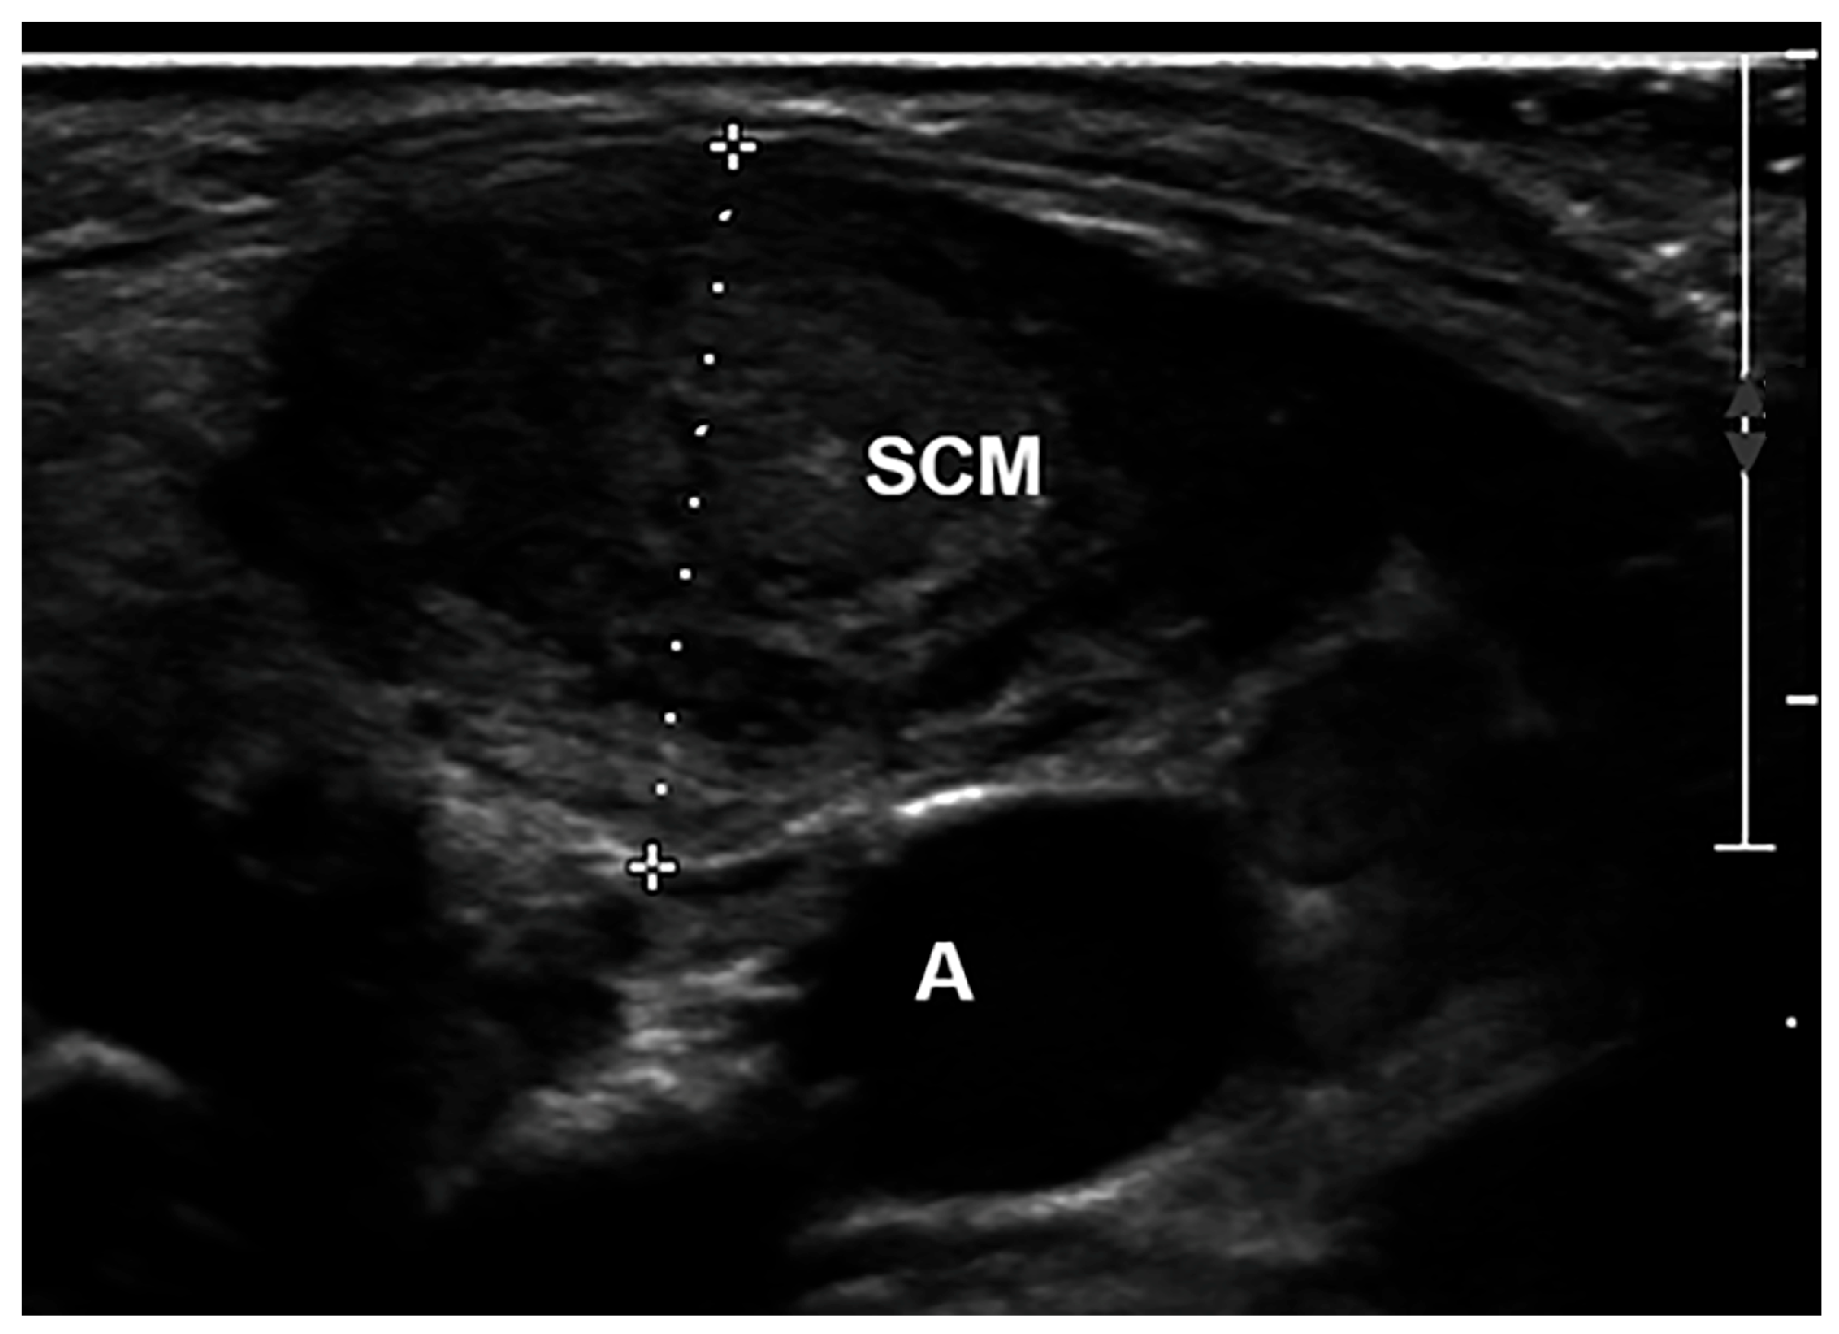

The thickness (Figure 2), defined as the distance between the superficial and deep aponeurosis in the thickest part of the impaired SCM, was measured on a transverse scan. SCM thickness of the impaired and normal sides was analysed using US pre-treatment and 3 months post-treatment. USG scanning was performed two times, and one typical image from the scan was utilized to determine the intra-rater reliability of the SCM thickness.

Figure 2. Ultrasound of the SCM. The thickness is the distance between the superficial and the deep aponeurosis of SCM. A indicates the carotid artery.